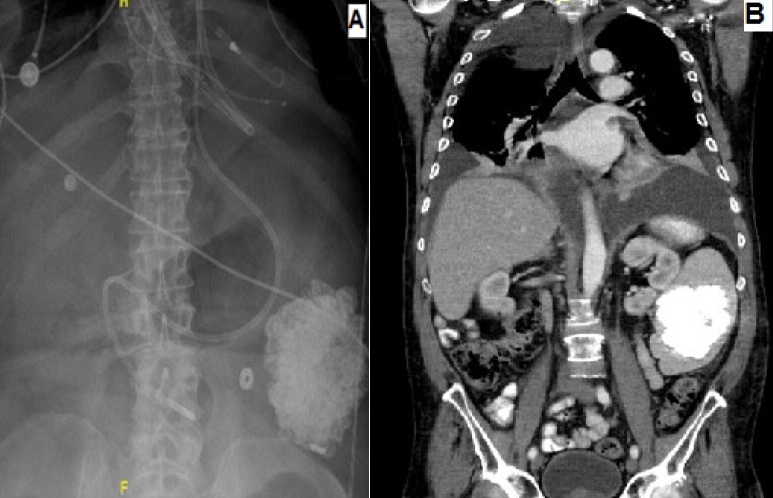

A 64-years-old male with medical history of hypertension, type II diabetes, coronary artery disease, and AL amyloidosis involving the heart, kidney and liver was admitted for decompensated heart failure, requiring Intra-Aortic Balloon Pump (IABP) and inotropic support. The patient was listed for heart transplant, but later developed cardiac arrest and required Veno-Arterial Extracorporeal Membrane Oxygenation (VAECMO) treatment. Abdominal X-ray was obtained to confirm the position of feeding tube which showed massive intra-peritoneal calcification (A). CT abdomen was obtained, and he was found to have extensive splenic calcification measures 8.9 x 7.1cm in cross-section and it spans 8.9 cm in craniocaudal direction (B). Spleen was impalpable on physical exam. Before the cardiac arrest, patient's renal function was at baseline, with the remaining of the basic metabolic panel normal. Hepatic function panel was significant for mild elevation in alkaline phosphatase and alanine aminotransaminases. All other laboratory work including coagulation and iron studies were normal. Nonetheless, patient's condition deteriorated over the course and he expired. Amyloid fibrils have an affinity to calcium and can result in calcific deposition in organs. Literature review showed that in amyloidosis, splenic calcification occurs in conjunction with other organs calcification especially liver. Thus this patient's case highlights the unique presentation of isolated massive splenic calcification without any other organ calcification with relatively normal laboratory and physical examination except findings consistent with his heart failure diagnosis.